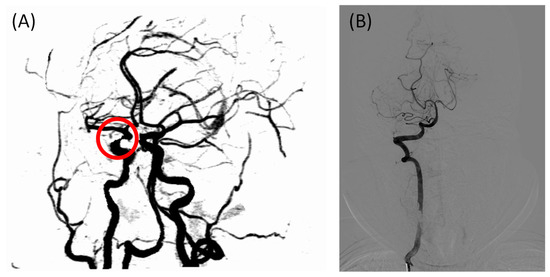

A total of 76 participants were included in this study; however, the sample size was not large enough to test the diagnostic efficacy of the FHR, and the sizes of the two groups were not well balanced because the positive cases outnumbered the negative cases in the hospital. Multi-center studies should be conducted in the future to expand the sample’s size. Another limitation of the statistical study is the lack of gold standard cerebral images; only two patients were diagnosed using DSA in this study because CTA/MRA is less invasive and expensive. One of the cases had different diagnostic conclusions from CTA and DSA, as shown in Figure 5. Due to a locally insufficient contrast agent, IICAS was misdiagnosed in the CTA scan. In contrast, the gold standard DSA showed no stenosis in that region. Interestingly, the FHR of the patient was within the normal range (below 0.360 on both sides), which was in accordance with the DSA diagnosis. If there are more similar cases in the positive group, the actual diagnostic performance of the FHR may be of higher quality. Therefore, more data labeled with DSA images should be collected in the future.

Figure 5. Incorrectly labeled case in the CTA scan due to an insufficient contrast agent, with the FHR in the normal range: (A) CTA image of the intracranial arteries of the patient, with the misdiagnosed intracranial internal carotid artery stenosis indicated in the red circle; (B) gold standard intracranial digital subtraction angiography image of the same patient showing no stenosis in the arteries, which is consistent with the FHR-based diagnosis. CTA, computed tomography angiography; FHR, first harmonic ratio.